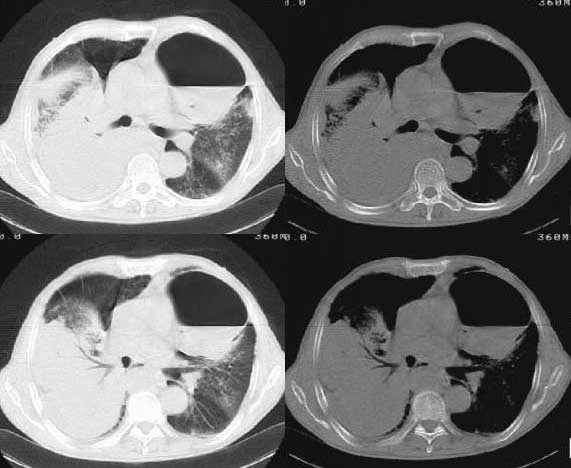

以下是引用woaixct在2006-6-23 12:15:00的发言:[br]第一张胸片示:右肺上叶为大片致密影占据,左肺上见大片致影及空洞性病灶并有液平;[br]第二张胸片示:左肺上叶致密影及空洞性病灶基本吸收,而右肺上叶之病灶有少许吸收改变;[br]ct片示:右上叶大片软组织密度,右肺门区至右肺上叶见巨大软组织块,内见支气管充气征,上纵隔右移,主气管及上叶支气受压变扁,中间支气管狭窄,左肺上叶空洞性病灶并有液平,左肺上叶尖后段见大片致密影,结合2张胸片考虑,ct片是4月份所摄,而不是6月份的片子;[br]结合2张胸片及ct片考虑:[br] 1.右中央型肺癌伴右肺上叶不张;[br] 2.左肺上叶尖后段炎性变及左肺脓肿;[br]第2张胸片提示:经过一个多月的不规则抗炎治疗,左肺上叶病灶及右肺上叶不张病灶基本吸收,而右肺占位无明显变化。

以下是引用jiangjing在2006-6-23 21:21:00的发言:[br]个人考虑还是两肺感染性病变可能大,主支气管及叶支气管是通畅的,并可见支气管气相;ct提示病变是以肺叶分布的,密度相对均匀;胸片可见有叶间裂下坠征,是不是考虑克雷伯杆菌感染可能.病人前后两张片比较病变是增多[应该考虑混合感染可能性大,右肺癌待排建议查痰及穿刺检查]